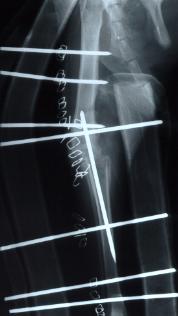

- pijltje wijst de verplaatste beenkam aan

- Het uitdiepen van de sleuf in de femur, hierbij wordt met een speciaal freestoestel de sleuf uitgeslepen en gepolierd. De patella komt dieper in de sleuf te liggen en kan niet meer luxeren.

- Verplaatsen van de beenkam op het onderbeen, hierdoor wordt de knieschijf meer naar buiten getrokken waardoor hij gemakkelijker in de sleuf van de femur blijft.